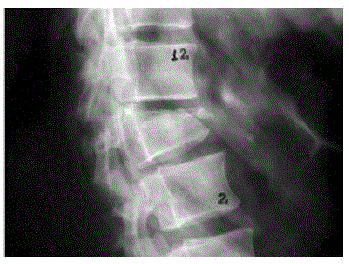

Paciente feminina, 65 anos, vem à consulta com queixa de dor lombar de forte intensidade, de início súbito, há 1 semana que relaciona ao esforço que fez para levantar um vaso grande em casa. Antecedentes de HAS, doença do refluxo gastroesofágico grave, 2 episódios prévios de trombose venosa profunda e insuficiência renal crônica em tratamento conservador (Clearance de creatinina = 26mL/min/1,73m2). Imagem de radiografia de coluna feita no dia anterior à consulta:

Qual tratamento deve ser prescrito para a condição que originou o quadro?